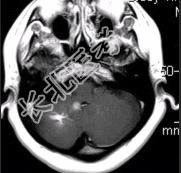

- 简答题4、MR增强检查如下图。请问最可能的诊断是什么?